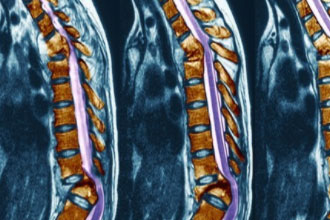

强直性脊柱炎是一种自身免疫性疾病,发作时会给患者带来不适与疼痛。如果不干预,时间长了会对脊柱造成严重的损害。那么,强直性脊柱炎应该如何治疗呢?你要知道以下知识。